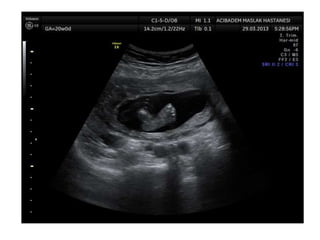

Amniotic band sequence:

Amniotic band sequence refers to a highly variable

spectrum of congenital anomalies that occur in

association with amniotic bands

Amniotic band sequence: Amnioticband sequence refers to a highly variable spectrum of congenital anomalies that occur in association with amniotic bands The estimated incidence of ABS ranges from 1:1200 to 1:15,000 in live births, and 1:70 in stillbirths